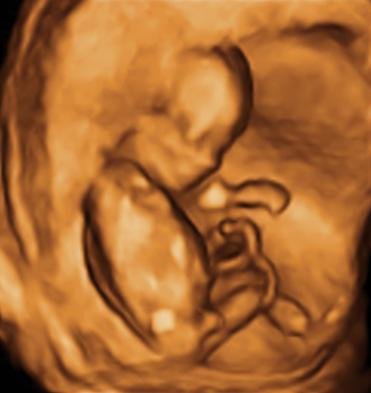

Ще си имам СИН !!!  newsm68 newsm44 newsm68 newsm44 newsm68 newsm44 newsm68 newsm44 newsm68 newsm44

Запознайте се с малкото ми момченце  Heart Eyes Heart Eyes Heart Eyes

Не мога да спа от радост. Вчера си го видях. Засега всичко ни е ОК.  Praynig Дай Боже и нататък да сме така  Praynig

МНОГО СЪМ ЩАСТЛИВА !!!

Термина се мести малко и става за 10 ноември  Peace